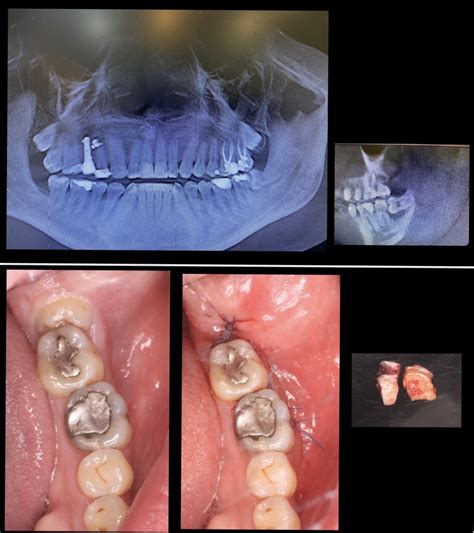

- Evaluación previa: Como siempre, lo primero es hacer un diagnóstico correcto. Radiografías y, en algunos casos, una tomografía para ver exactamente dónde está el diente y su relación con las estructuras vecinas. Esto nos ayuda a planificar la intervención de la manera más segura posible.

- Incisión y extracción: Aquí es donde puede variar un poco. Dependiendo de la posición del diente, el dentista hará una pequeña incisión en el paladar para acceder al diente. Si está muy atrapado o es grande, es posible que necesite dividirlo en partes más pequeñas para sacarlo de manera más fácil.

- Suturas: Al finalizar, puede que necesitemos poner algunos puntos de sutura. Estos puntos suelen ser reabsorbibles, así que no te preocupes porque no tendrás que volver solo para quitarlos. La herida cicatriza bien con los cuidados adecuados.